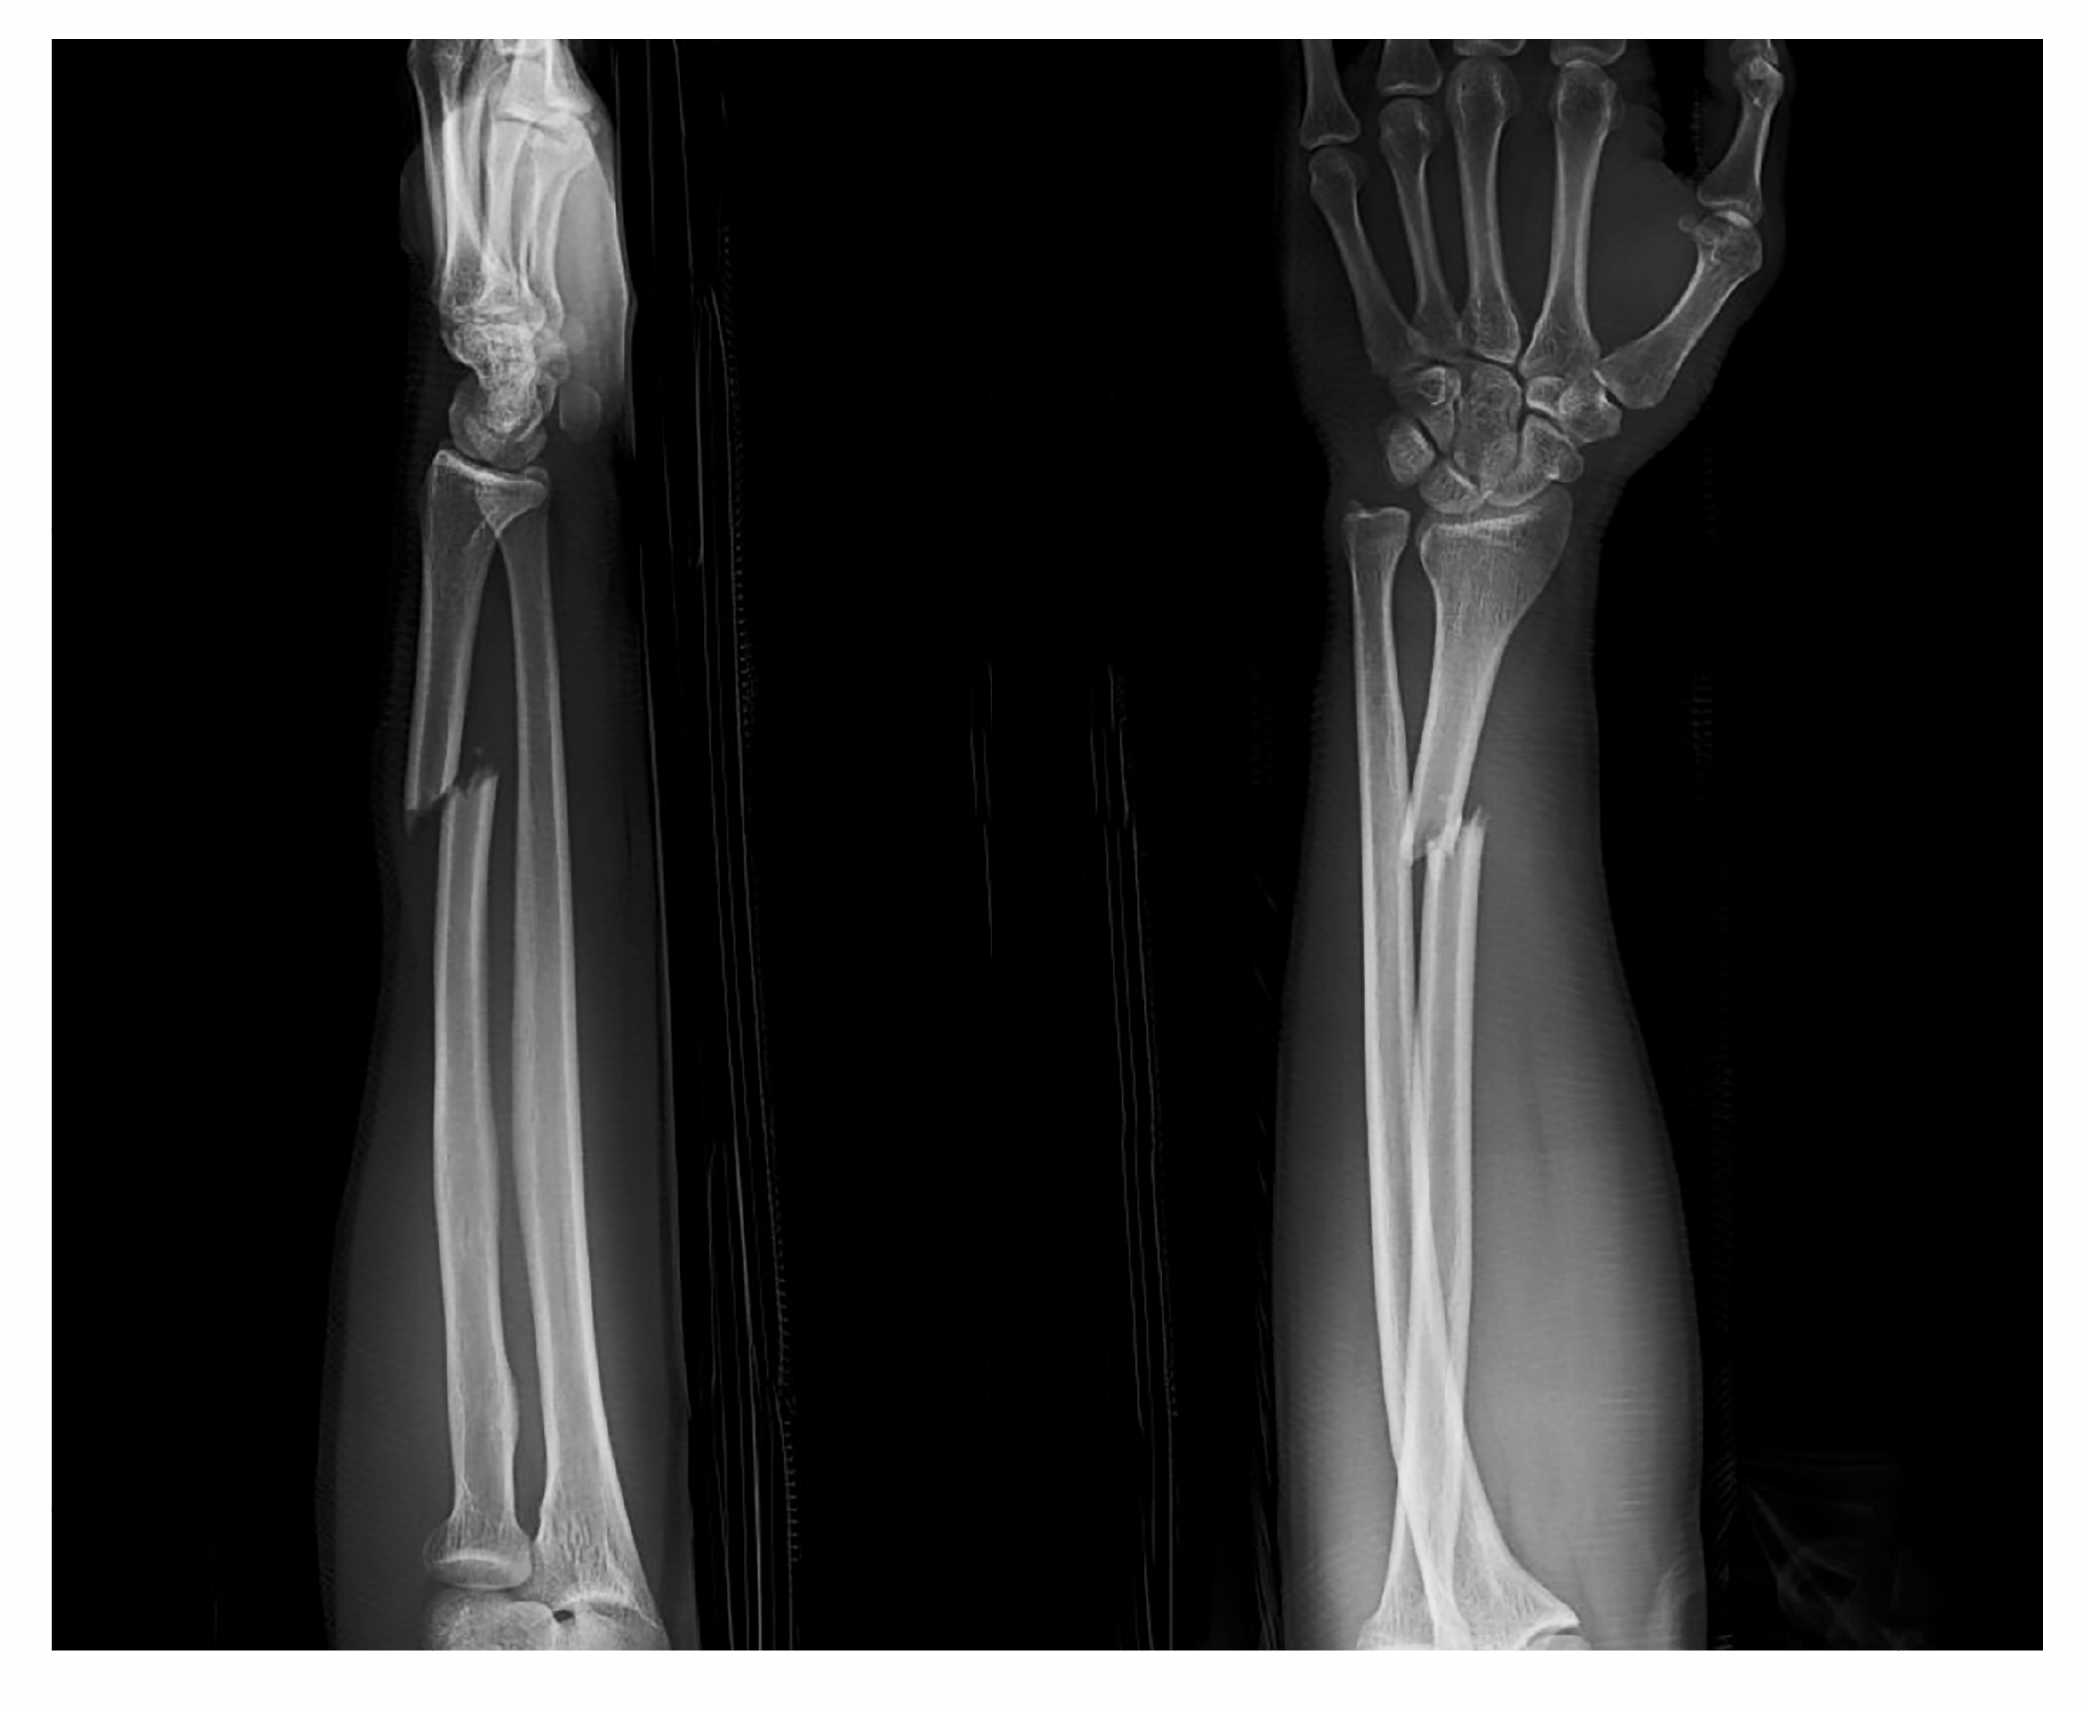

A 16-year-old boy presents to the ED with acute left knee pain. He was riding his bicycle when his back tire was hit by a car. He reached his left leg outward while attempting to prevent his bike from falling and felt a “pop” and then excruciating knee pain. The patient is lying in bed with his left knee slightly bent, but he is unable to move the leg or knee. There are no obvious bony deformities. You feel boggy swelling and tenderness over the patellar region. His lateral knee X-ray is shown above. What is the most likely diagnosis?

Patellar tendon rupture